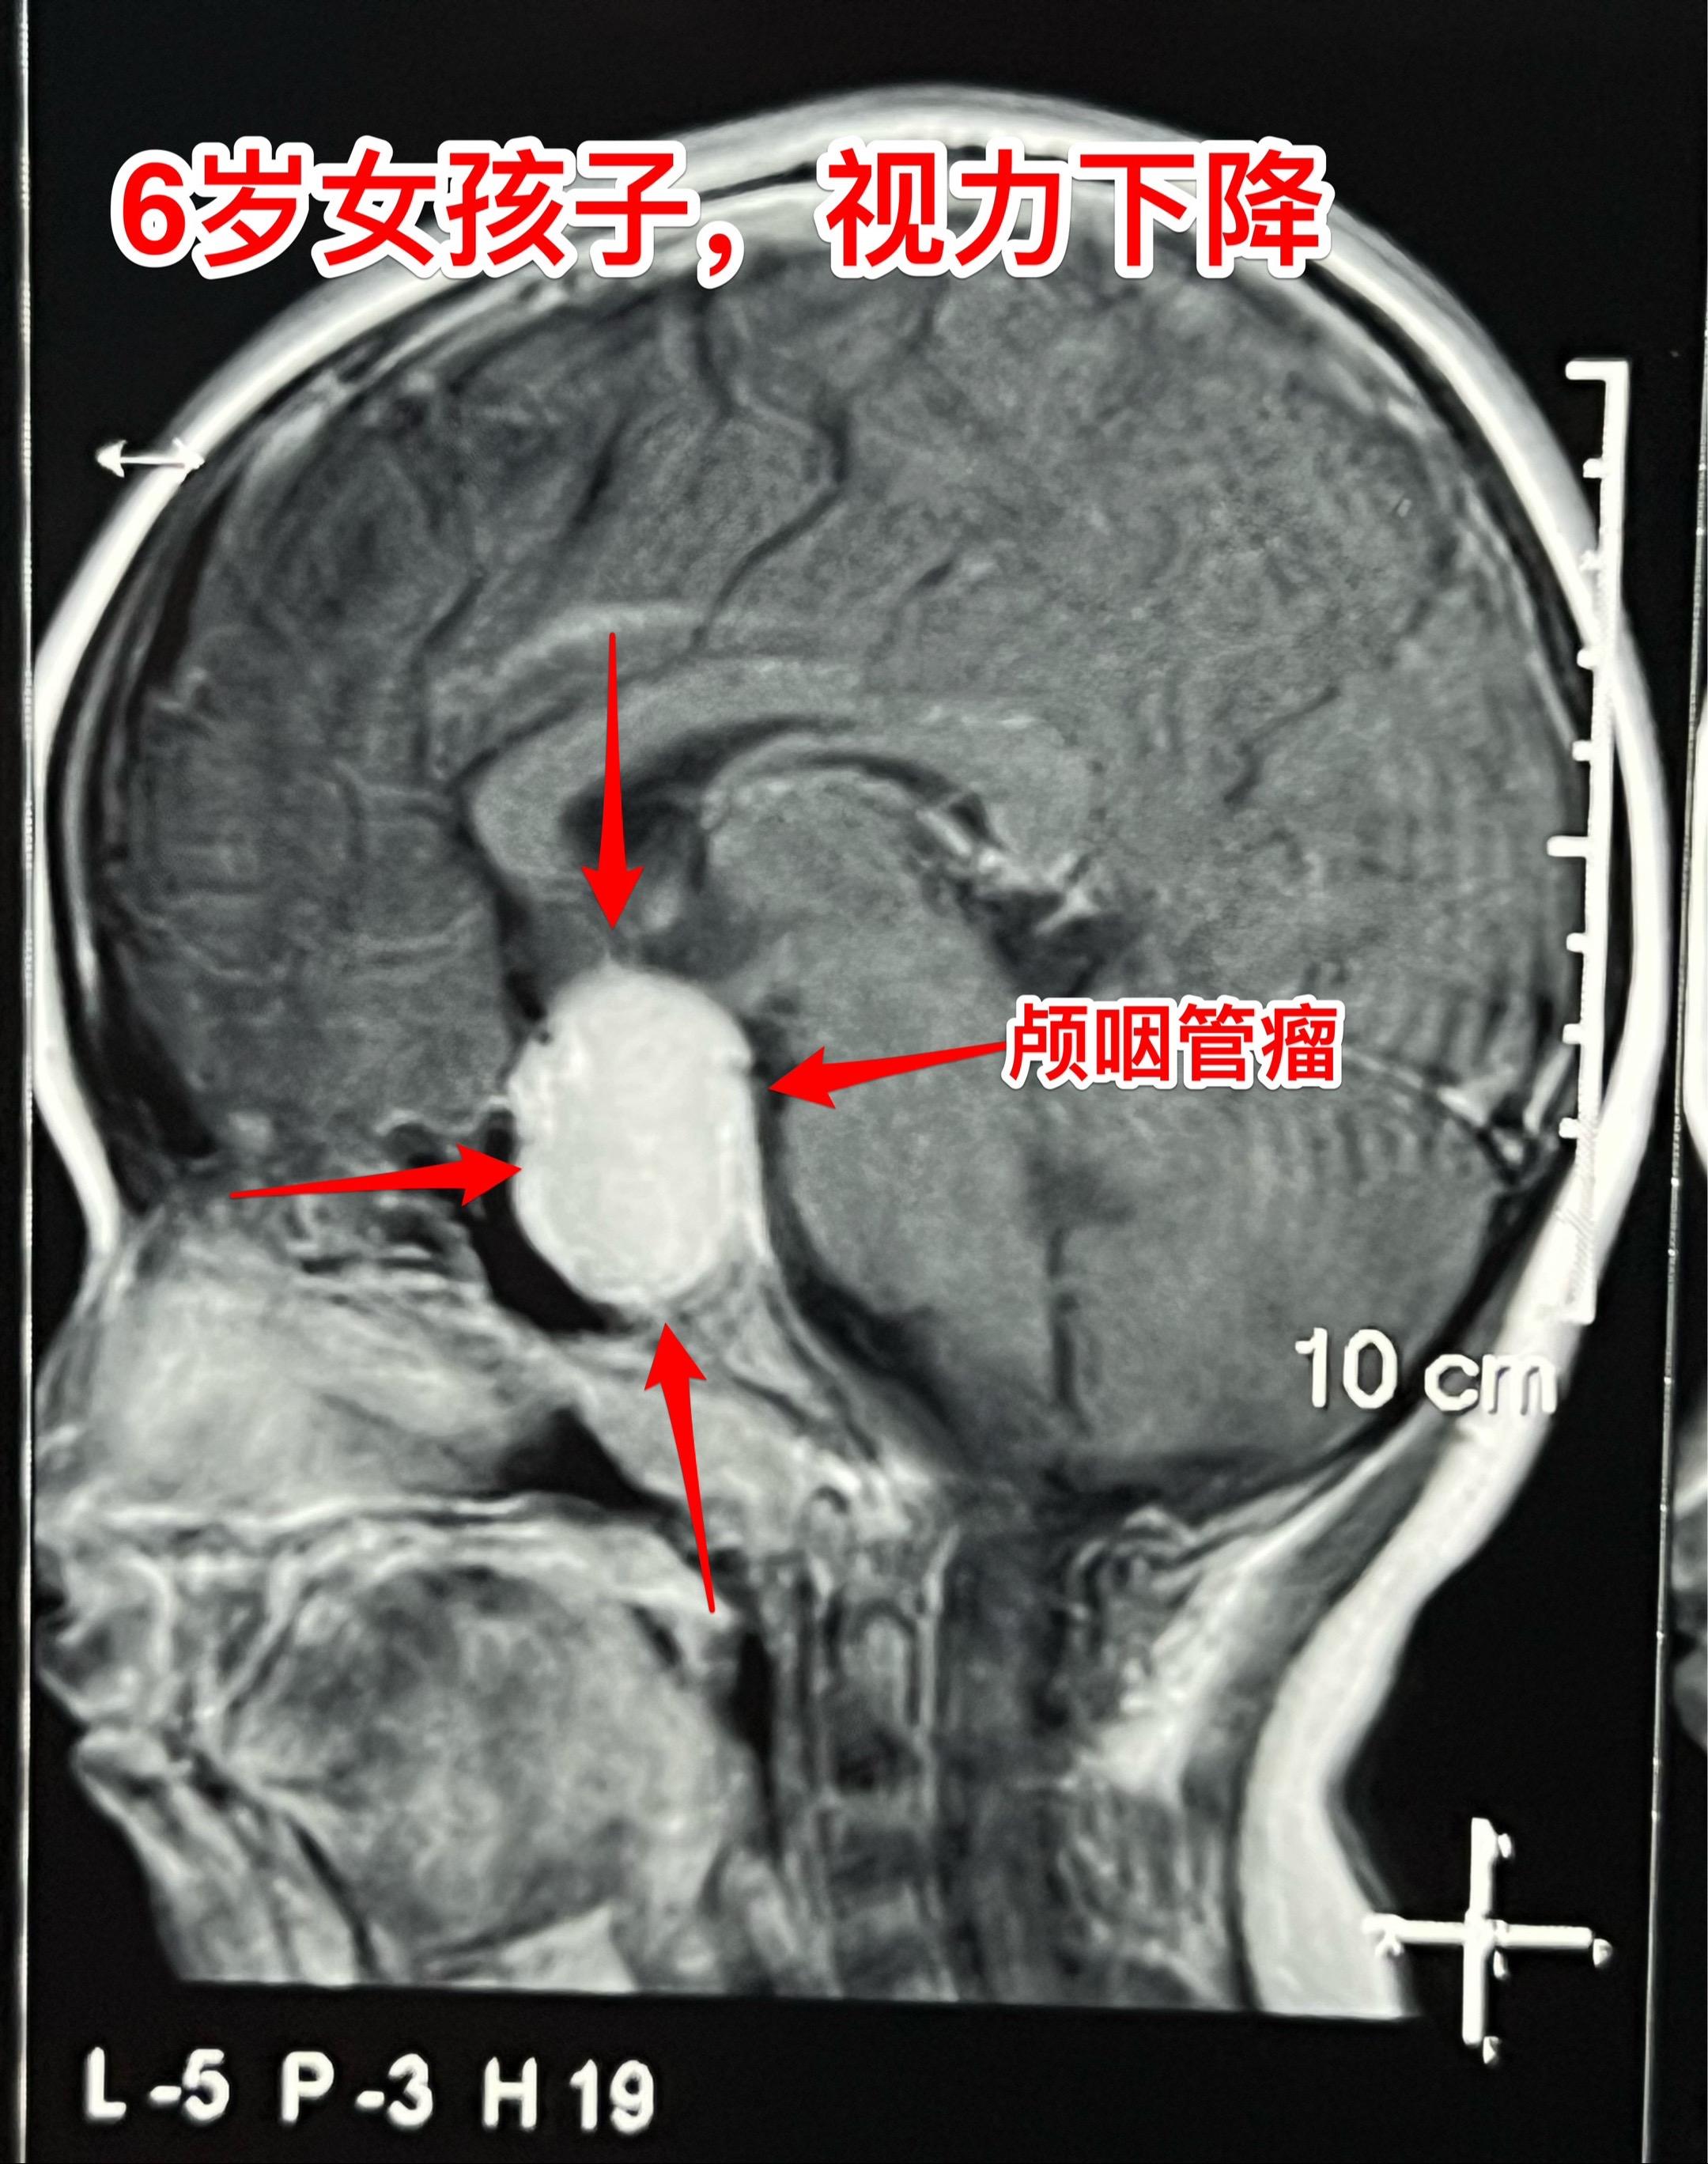

小学生的视力家长一定要关注。小学生因岁数小,对视力下降很可能并不知道表...

2025-03-02 07:52